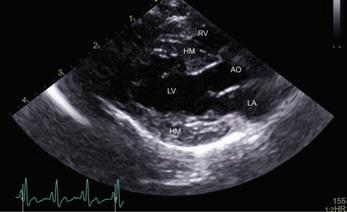

An ultrasound image (echocardiogram) shows the heart of an elderly cat. The labeled structures are the heart’s chambers. The graph at the bottom is an electrocardiogram (ECG), monitoring the heart’s electrical activity during the scan. This image helps veterinarians assess the heart’s function and structure, which is crucial for differentiating normal age-related changes from potential heart disease in older cats. (LA: left upper chamber, or left atrium; LV: left lower chamber, or left ventricle; HM: heart muscle; AO: aorta, the main vessel leaving the left side of the heart; RV: right lower chamber, or right ventricle.)